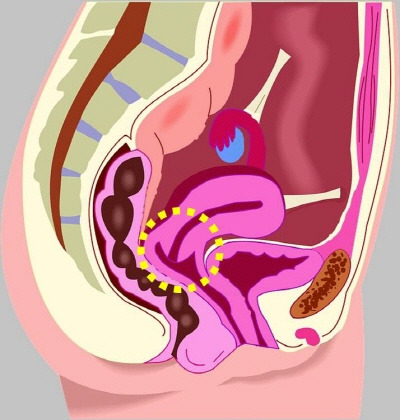

노란색 원이 그려져 부분이 자궁경부(cervix of uterus)입니다.

자궁경부암 검사는 피검사가 아니라 자궁경부의 세포를 채취하여 검사를 시행하므로, 다리를 벌리고 검사합니다(쇄석 위 자세). 산부인과 검진을 하게 되나 개인적으로는 남자의사를 선호하는지라, 남자 선생님께 진료 보도록 아내를 설득하였습니다. 남자 선생님이 불편하다면 여자 의사 선생님께 진료를 보면 됩니다. 자궁경부에 이상이 있는지, 만져지는 복강 내 종괴가 있는지 검진을 하게 됩니다. 상당수 여성에서 불편함을 느끼는 것 같습니다. 마음의 준비를 하고 진료를 보시러 가시길 권유드립니다.